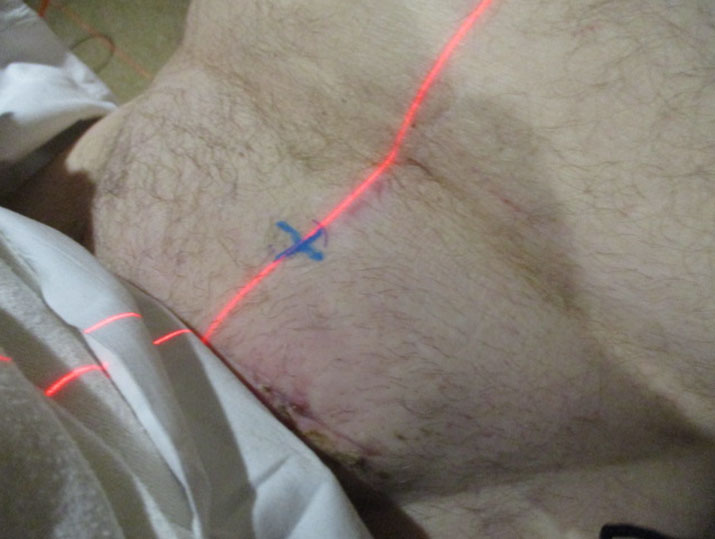

Axial computed tomography (CT) imaging through the left groin demonstrated a small low-density nodule in the inguinal canal, initially believed to be fluid in a small hernia sack (Figure 1). After rapid clinical growth, an ultrasound image of the same mass demonstrated a solid lesion having significantly grown as the preceding CT (Figure 2). A fine-needle aspiration was performed with inconclusive results. Due to further enlargement, an excisional biopsy was performed with a partial excision after which the patient developed wound complications. The post-operative infection was treated with debridement and re-opening of the initial incision with later closure.

Figure 1: Axial CT imaging through the left groin demonstrates a small low-density nodule in the inguinal canal, initially believed to be fluid in a small hernia sack.